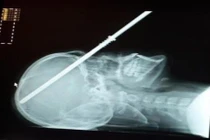

Bệnh viện Sản - Nhi tỉnh Quảng Ngãi vừa gắp thành công dị vật là chiếc kẹp tóc bằng kim loại trong bụng bé gái 6 tuổi.